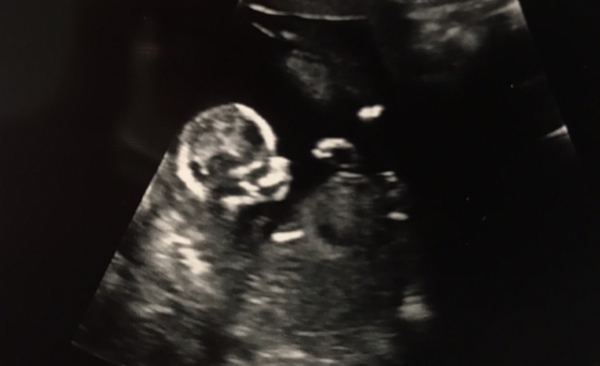

Had my scan this morning at 9 weeks due to spotting but all is well and baby is measuring as expected. Appointment was half hour late and then they prodded me lots as they were testing out a new machine. Thought I was going to wet myself but just so pleased everything is OK! Attached pic not that you can really see much!!

@MonicaGellerHyphenBing hope your day gets better and triage are helpful. Me and the disabled work loo are getting very well acquainted too!

Had our dating scan today... was extremely exciting to see and we have an extremely active baby. Due at the beginning of Jan 🤗

Jan 2020 - Thread 4

Anyone have thoughts on gender?!